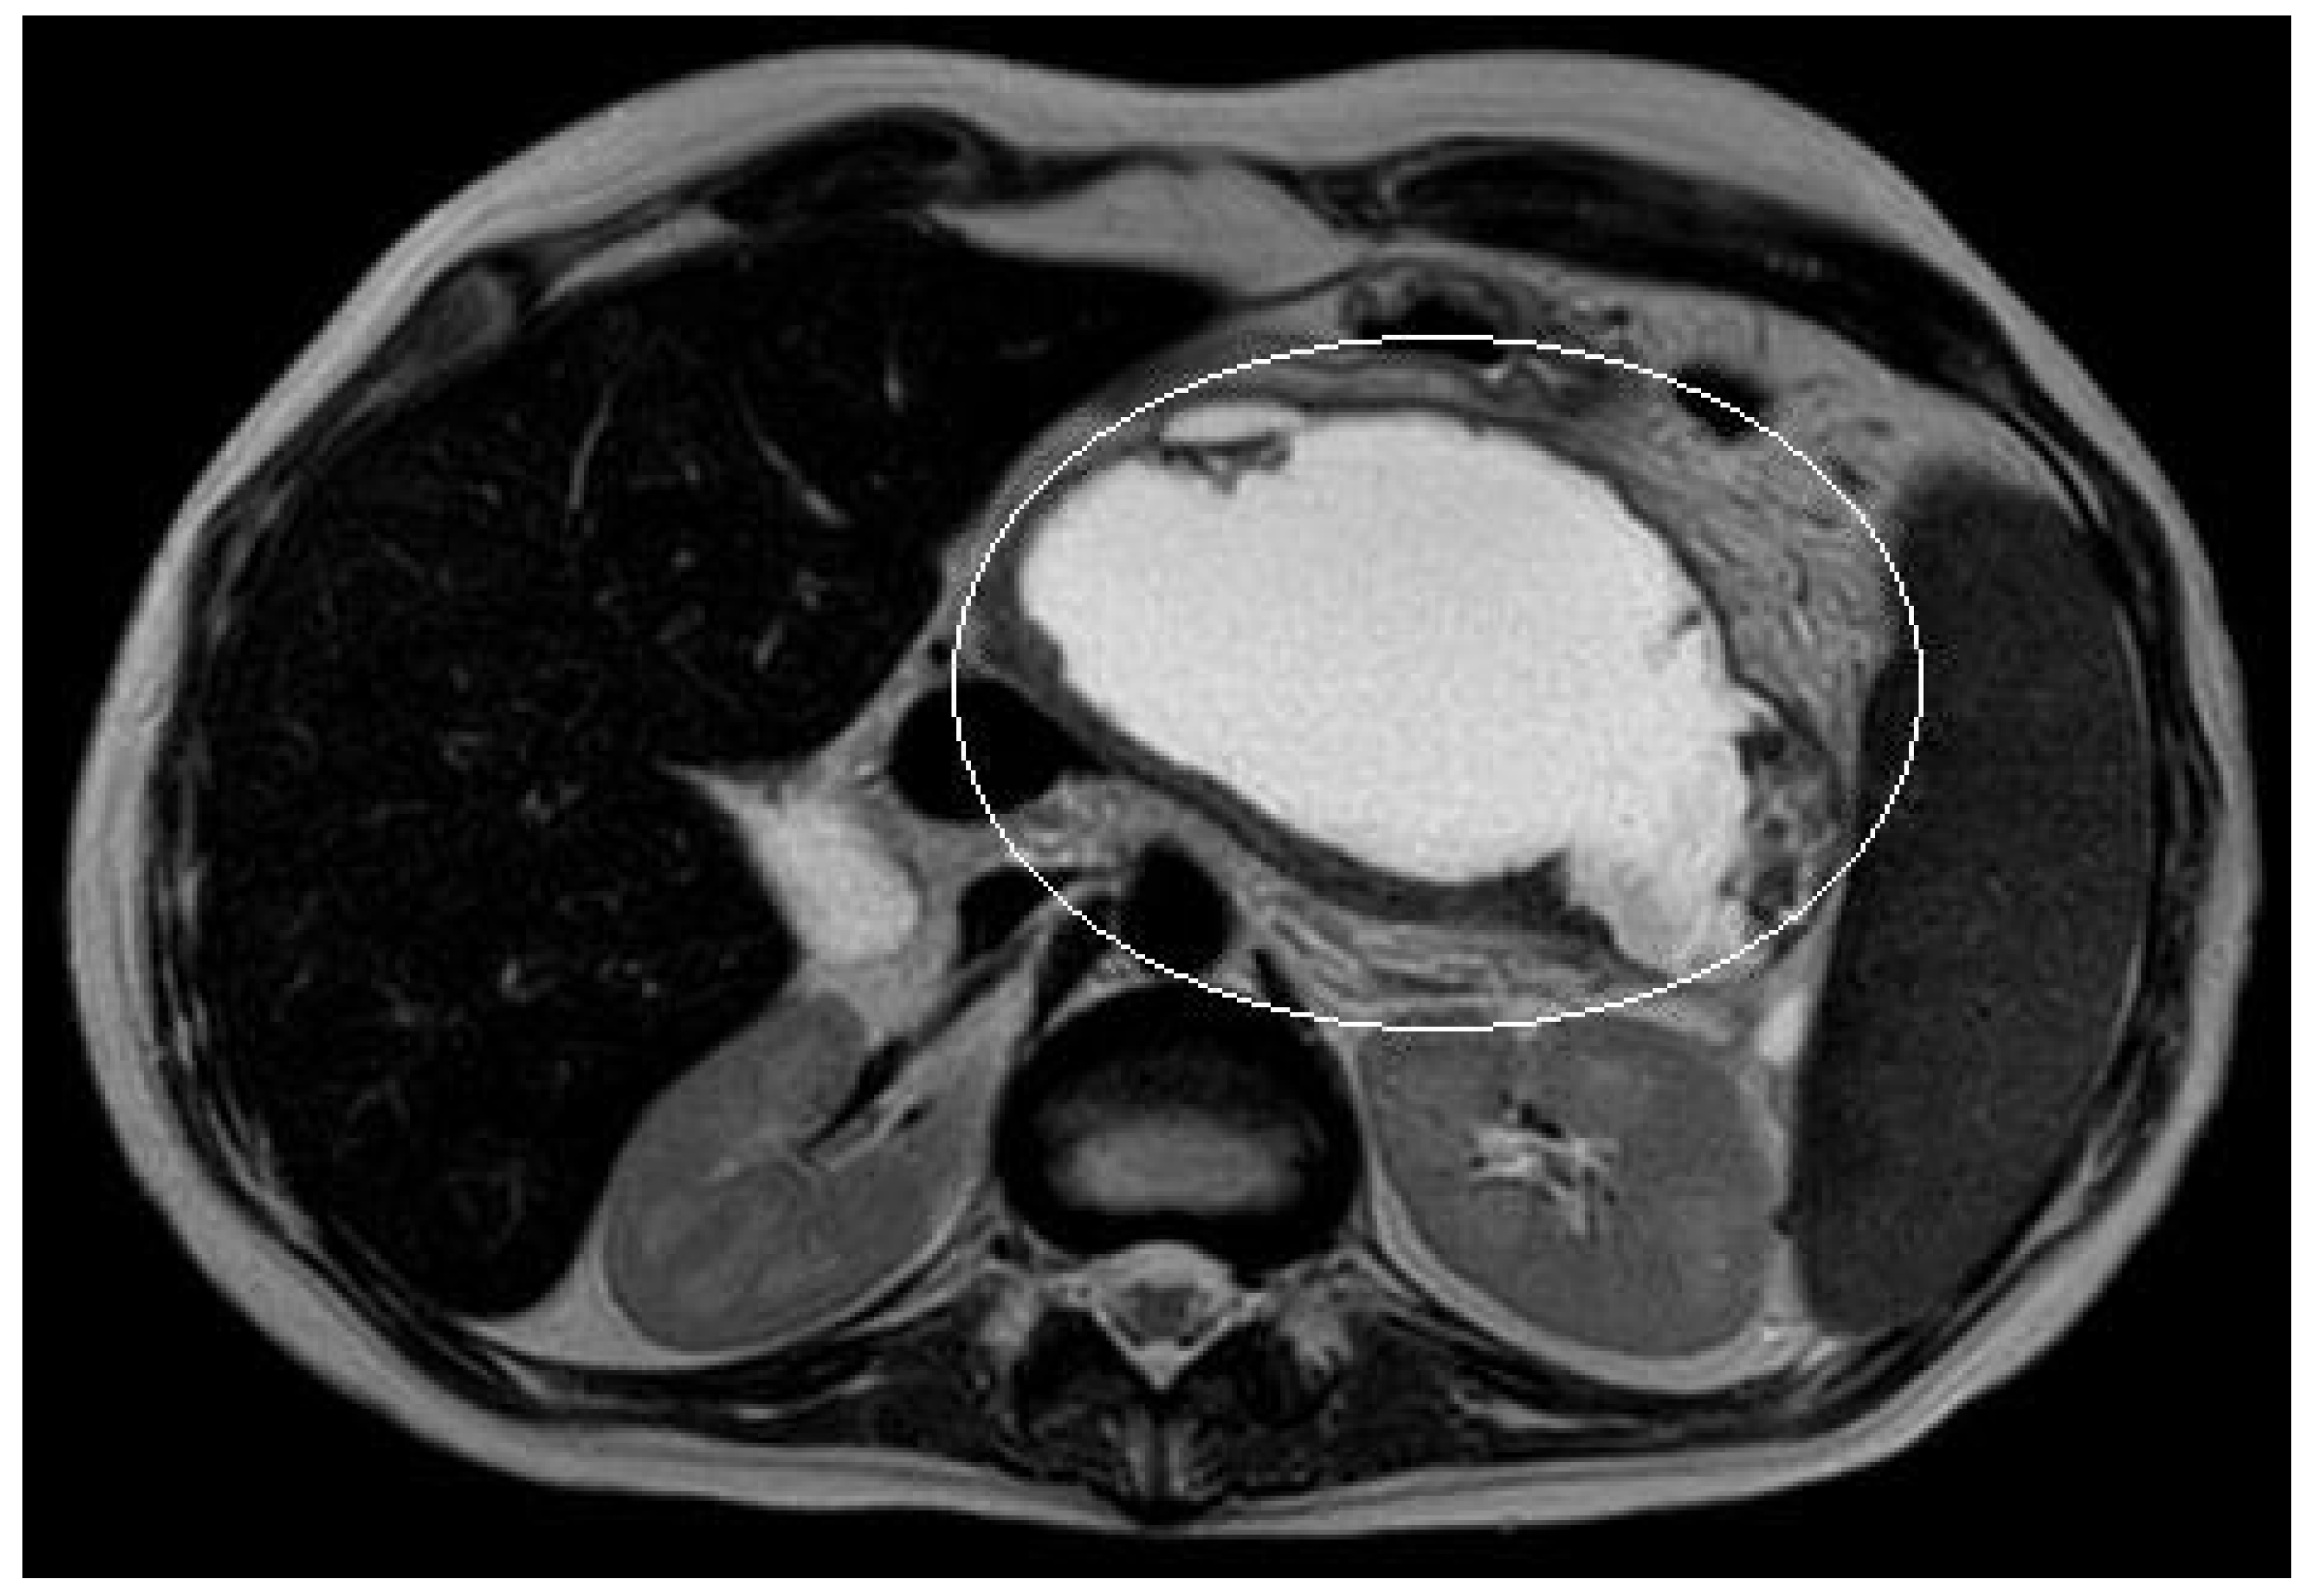

3.1.2. Patient n°2

A 15-year boy was affected by B-acute lymphoblastic leukemia and severe coagulopathy; he developed a chemotherapy-induced acute cholecystitis, acute pancreatitis complicated by septic shock and PFC. At MRI the major diameter of the collection was 12 cm (Figure 4). After unsuccessful attempts of conservative treatment, the boy underwent two different attempts of EUS-guided trans-gastric pseudocyst puncture and liquid aspiration, within a month between the two procedures. few days after the second one, the PFCs persisted and the boy still presented abdominal pain and fever. As the need to not delay chemotherapy was pressing, the patient underwent EUS-guided cystogastrostomy and EC-LAMS positioning as a rescue procedure. Post-operative course was uneventful. MRI performed 14 days after the procedure showed a significant reduction of the pseudocyst, which was no longer visible on the ultrasound performed right before its removal. EC-LAMS stayed in place for a total of 28 days and was endoscopically removed, without any intra-operative or post-operative complication.

Figure 4.

Patient n°2 MRI. Pseudocyst with maximum diameter 12 cm in the left hypochondrium in close proximity to the posterolateral wall of the stomach.